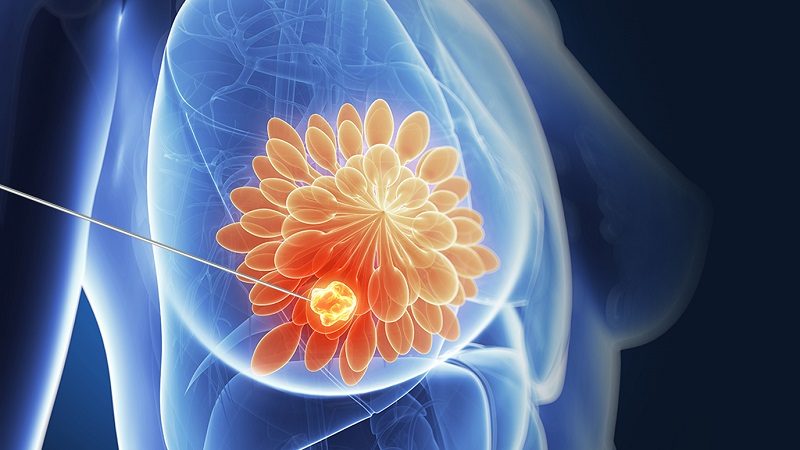

پستان، اندامی است که در قسمت سینه انسان وجود دارد و در مورد خانم ها، این اندام رفته رفته با افزایش سن بزرگ تر می شود تا به اندازه ثابتی برسد. پس از رسیدن به سن بلوغ در دختران، این اندام شروع به رشد می کند و در هنگام بارداری و حاملگی، به دلیل تغییرات هورمونی که در بدن زنان صورت می گیرد، و با بالا رفتن هورمون پرولاکتین در خون زنان، این اندام بزرگ تر و حجیم تر می شود. برای این که اندام پستان بتواند شیر مورد نیاز برای نوزاد را فراهم کند، بایستی این اندام به اندازه کافی بزرگ شده باشد و نوک پستان یا در اصطلاح پزشکی،گی مناسبی از بافت پستان داشته باشد.

در بعضی موارد ممکن است کیست هایی در این بافت ظهور کنند. عمل لیزر کیست پستان، یکی از جدید ترین و بهترین عمل هایی است که برای از بین بردن این کیست ها در اندام پستان، می توان از آن استفاده کرد و ظرف مدت چند ساعت، تمام کیست هایی که در پستان به وجود آمده و شکل گرفته اند، به کمک این روش از بین برده خواهند شد. بافت پستان دارای قسمت های مختلفی می باشد که در پستان های طبیعی، همه ی این قسمت ها وجود داشته و به عنوان اجزای اصلی پستان شناخته می شوند. حال آن که کیست ها و توده ها، اجزای مزاحم و غیر آشنایی در این اندام بوده که در شرایط گوناگون، می توانند پیامد های مختلفی را به دنبال داشته باشند. در این مقاله قصد داریم تا شما را با عمل لیزر کیست پستان آشنا نموده و درباره علائم کیست پستان، هزینه لیزر کیست پستان و همچنین مراقبت های بعد از این عمل نیز توضیحاتی را ارائه دهیم. با ما همراه باشید.